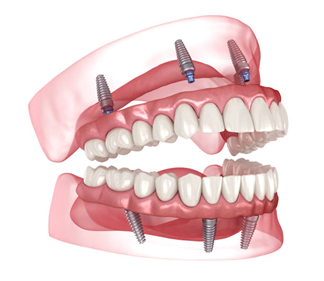

All-on-4 Dental Implants

A modern solution for full arch restoration using only four implants. All-on-4 implants are strategically angled to maximize bone support, making them ideal for patients with reduced bone volume — often eliminating the need for bone grafts.

All-on-6 Dental Implants

Similar to All-on-4 but with six implants per arch for additional support and load distribution. This option is recommended when higher strength or a broader prosthetic base is required, especially in the upper jaw.